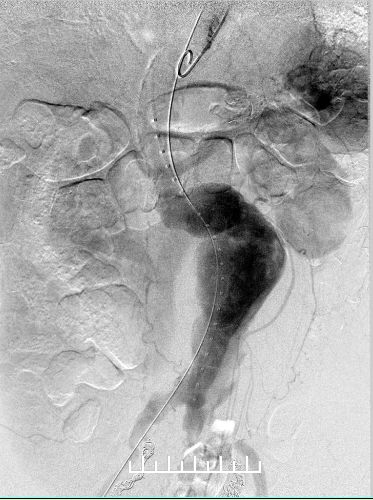

使用全穿刺技术(Preclose技术),建立双侧股动脉及右侧肱动脉入路。“全身像”显示:瘤颈成角约90度,左侧髂总动脉钙化扭曲严重,双侧髂内动脉显影,左侧髂内动脉瘤。

右肾动脉闭塞,精确定位左肾动脉开口释放支架。